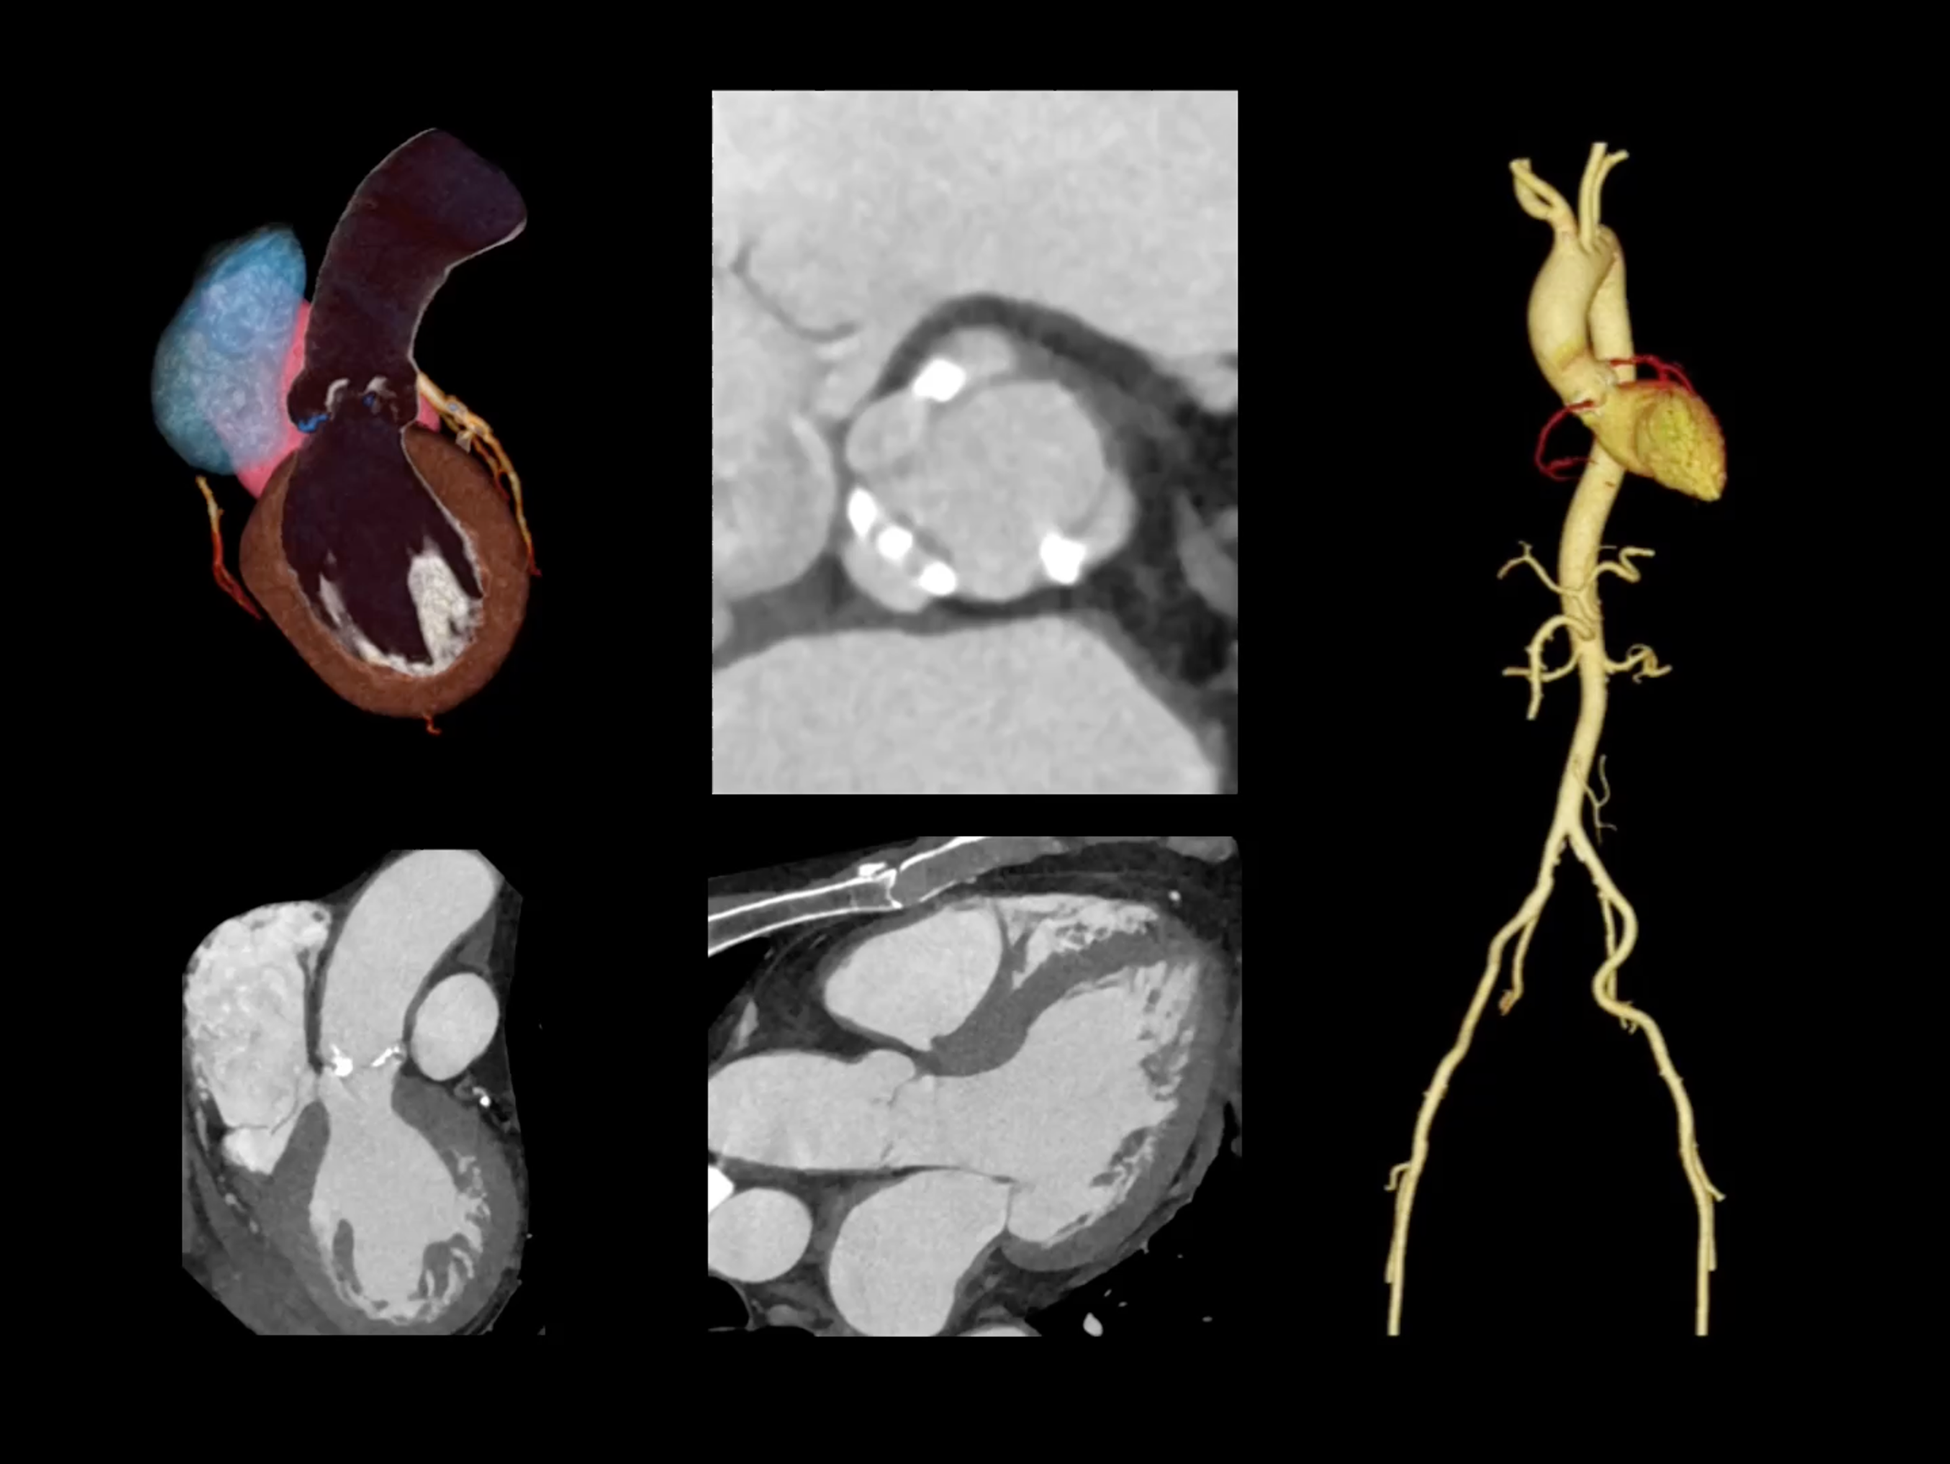

uCT SiriuX® 挑战心脏成像时间分辨率的极限,精准捕捉心脏全周期的动态变化。无论静态解剖形态,还是动态功能表现,都能清晰呈现,让心脏不再是“定格”的器官,而成为可视的生命律动。

CardioCapture 2.0 通过“识别–追踪–建模–校正”的完整流程,精准分割心脏结构,动态追踪运动轨迹,并构建多时相运动场,最终实现冠脉、瓣膜、心肌及心室结构的同步校正,清晰洞见每一次心跳细微变化,真正将心脏动态掌握于毫秒之间。

CardioCapture 2.0 在目标时相前后重建多时相影像,通过深度学习网络精准提取冠脉中心线,进而建立时相间运动模型,实现对冠脉分段图像的精准运动校正。

CardioCapture 2.0 可对心肌、瓣膜及心室等结构进行同步运动校正。基于深度学习的心脏精细分割,实现了更完整的心脏全局信息提取,能有效抑制全心运动伪影,显著提升心脏细节的清晰度与诊断可靠性。

心脏成像,自由掌控

uCT SiriuX® 以 8ms 全心等效时间分辨率与16cm宽体覆盖,突破传统心脏成像局限,完整呈现搏动中的心脏结构与动态功能;配合无心电门控扫描与智能化工作流,更使心脏检查摆脱心率、配合度与操作复杂度的束缚,实现真正自由从容的成像体验,为临床功能评估提供更深层依据。

全心4D电影成像

提供全心动周期内多个时相的清晰结构成像信息,动态展示心脏结构运动变化。

全心全时相高清成像

单心动周期内的任意时相获取高质量的冠脉CTA图像,确保稳定的心脏成像效果。

单时相无心电冠脉成像

在更短单时相曝光下,实现自由呼吸、无门控的冠脉CTA成像,以低剂量、无门槛的方式,重塑心脏扫描体验。

一站式心脏多维成像

一次对比剂注射可同时获取冠脉CTA、心肌灌注和心肌延迟强化等多维图像信息。